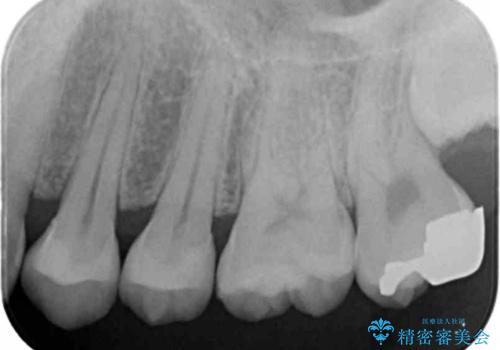

- 外から見える範囲の銀歯のやり替えをご希望で来院されました。

セラミックインレーでの治療となります。

- 左上45 セラミックインレー 77,000円×2本 費用は治療当時の料金となります